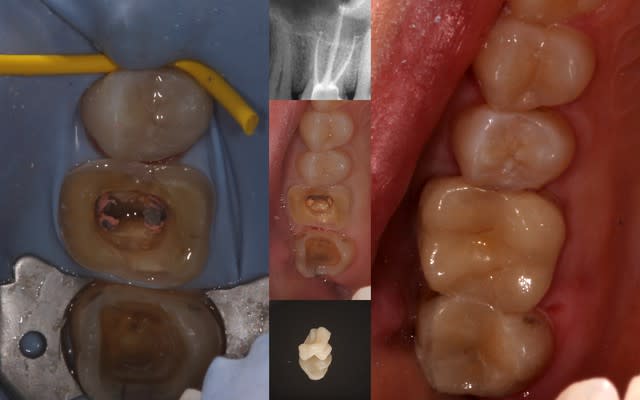

La séance prévue était: dépose d'un volumineux amalgame sur 16, curetage des caries sur 16 et 17, inlay cerec 17 + retraitement de 16 et reconstitution à tenon. Couronne dans une 2e séance.

A la dépose de l'amalgame, j'avais des parois résiduelles suffisamment épaisses et une cavité d'accès profonde permettant d'envisager une endocouronne.

De ce fait, changement de chronologie:

- curetage des caries

- repérage des entrées canalaires et mise en forme de la cavité d'accès

- préparation pour l'inlay et l'endocouronne (avec des limites supra)

- empreinte optique et mise en route de l'usinage

- pose de digue

- rte 16 pendant que le cerec bosse tout seul

- collage des 2 éléments sous digue

et voili, voilou, content de la séance, café mérité

Il y a sans doute beaucoup à critiquer, mais mon bilan c'est quand même beaucoup de temps de gagné et une étanchéité coronaire obtenue avant la dépose de la digue.